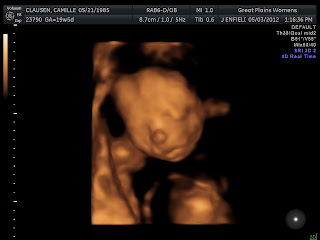

20 weeks 5 days. Today marks the day of the last pregnancy when we found out the worst news of our lives...that we had lost our baby...our sweet, beautiful daughter.

It's hard to believe that it's been 7 months since then...and 5 since I've written. In that time, we've come so far on our very emotional journey of attempted parenthood. In that time we've begun a new life, almost lost it, waited out the unknown for 9 agonizing weeks, and finally...hit and passed the "halfway" point.

This baby has continued to give me a precious gift every single day from week 17 on. The gift of movement...constantly. With each flutter, each kick, each punch washing away the doubt and fear and paranoia that crawls into the cracks of my soul and hides there. And of course, this movement tends to be at the most inconvenient times...like now, in the middle of the night, with a full busy day ahead of me tomorrow. I don't care, I'll take it. I cherish it. I wait for it.

I'm finally allowing myself to get excited, allowing myself thoughts of bringing this baby home...of holding this baby, feeding this baby, walking the floors through the night running on no sleep with this screaming baby. I want this child in my arms so bad sometimes that it aches. Halfway! We are halfway to you.